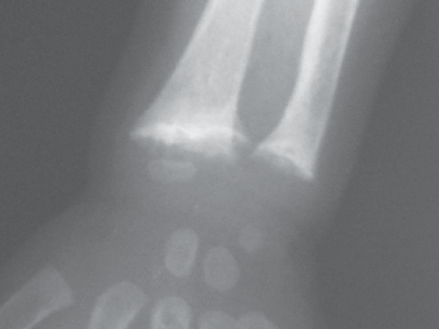

Examination reveals an otherwise healthy African-American boy with genu varum. Radiographs of the wrists are ordered.

ANSWER: Vitamin D Deficiency Rickets

The radiograph shows cupping, fraying, and widening of the metaphysis. Further evaluation reveals normal blood calcium and phosphorus levels; however, the level of alkaline phosphatase is markedly elevated and the 25-hydroxyvitamin D level is very low at 5 ng/mL. This child had not received vitamin D supplementation, was dark-skinned, and lived in Michigan where he spent most of his first 12 months of life indoors with a lack of sun exposure—factors that point to a diagnosis of vitamin D deficiency rickets.

Skeletal manifestations associated with rickets are seen first at growth plates of rapidly growing bones (eg, wrists, knees). Patients can have enlarged wrists and ankles and bowing of legs. Widening of the epiphyseal plates is an early radiographic change. This may progress to cupping, splaying, or stippling of the metaphyses. With severe disease, the shafts of long bones become osteopenic and predispose patients to pathological fractures.3